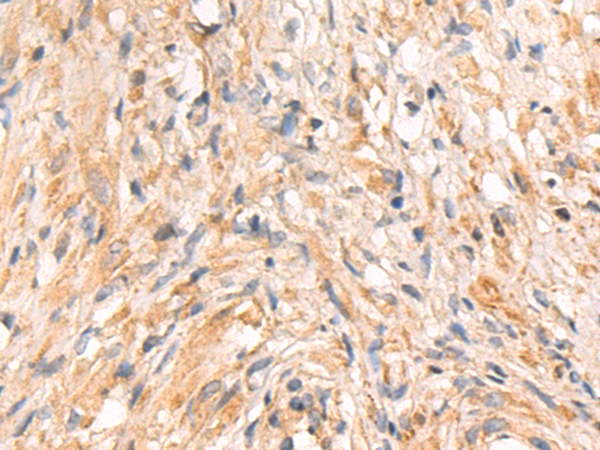

分类: 科研抗体货号: P08971别名: VIL; D2S1471应用: WB,IHC反应种属: Human